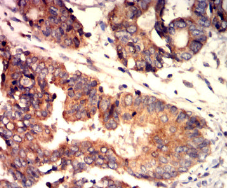

IHC    1/200-1/1000